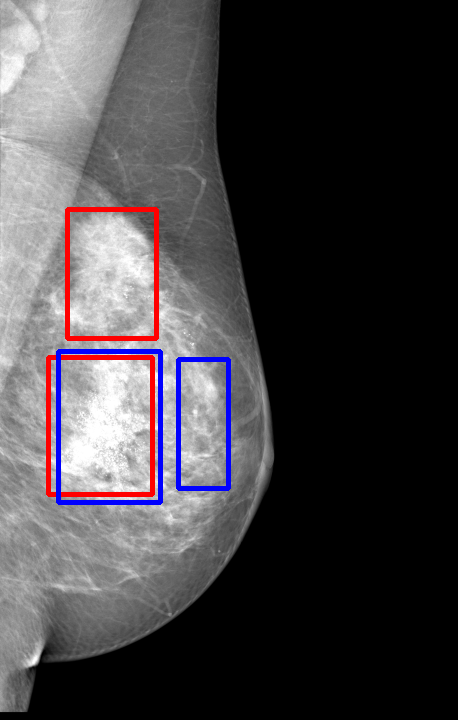

UDA has been extensively studied in case of natural images, utilizing techniques such as adversarial learning [21],pseudo-label training [6, 21, 40], image-to-image translation [40], graph reasoning [20], and adaptive mean Teacher training [6], improving domain adaptation efficiency of object detectors. Recently multiple works focused on using Mask autoencoders (MAE) methods in large-scale pretraining for vision models, involving masking parts of input and reconstructing them [12, 33]. However, these approaches overlook domain shifts. Alternatively, widespread utilization of Teacher-Student models, wherein a Teacher provides pseudo-labels for target domain (unlabeled images) to supervise a Student model, leads to notable adaptation improvements [40, 43]. However, these techniques face the challenge of incorrect predictions and excessive false positives per image due to low-quality pseudo-labels, particularly for medical imaging problems. Pseudo-labels are filtered from the Teacher model’s outputs based on the confidence score threshold. Selecting numerous pseudo-labels with low thresholds leads to inclusion of incorrect predictions, and compromising performance. Conversely, higher thresholds yield a limited number of pseudo-boxes, resulting in sub-optimal supervision. Existing Teacher-Student models often produce pseudo-labels riddled with errors and false positives, as illustrated in Fig. 1(a) and Fig. 1(b). Though [21, 40, 43] utilize techniques like adversarial alignment, weak-strong augmentation, and selective retraining of Student model to minimize the false positives in pseudo-labels, these approaches fail on medical images.

Contributions of this work. We note that screening mammography inherently differs from natural images, with breast abnormalities such as masses, asymmetries, and micro-calcifications, typically much smaller in comparison to the salient objects present in natural images, emphasizing the need for approaches specific to this problem. To address these issues, we make following contributions in this work: (1) We introduce D-MASTER, a transformer-based Domain-invariant Mask Annealed Student Teacher Autoencoder Framework for cross-domain breast cancer detection from mammograms (BCDM), integrating a novel mask-annealing technique and adaptive confidence refinement module. Unlike pretraining with mask autoencoders (MAEs) [12], leveraging massive datasets for training and then fine-tuning on smaller datasets, we present a novel learnable masking technique for the MAE branch that generates masks of different complexities, which are reconstructed by the DefDETR [44] encoder and decoder. Our approach, as a self-supervised task on target images, enables the encoder to acquire domain-invariant features and learn better target representations as shown in Fig. 1(c). (2) In Teacher-Student model, since the pseudo-label noise generated by the Teacher affects the Student model severely, we propose an adaptive confidence refinement module that progressively restricts the confidence metric for pseudo-label filtering. During the initial adaptation phase, soft confidence is applied allowing more pseudo-labels to learn better target representations. Subsequently, as confidence gradually increases, the focus shifts towards enhancing detection accuracy by prioritizing more reliable pseudo-labels. (3) We release a bounding box annotated subset of 1000 mammograms from the RSNA Breast Screening Dataset (referred to as RSNA-BSD1K) to support further research in BCDM. (4) We setup a new state-of-the-art (SOTA) in detection accuracy for UDA settings. We report a sensitivity of 0.74 on INBreast [25] and 0.51 on DDSM [18] at 0.3 FPI, compared to 0.61 and 0.44 using current SOTA respectively. Significant performance gains are also observed on our in-house and RSNA-BSD1K datasets.